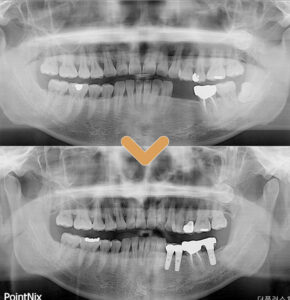

환자분의 경우에도 신경관에

손상이 갈 수 있음에 대한 가능성을

충분히 설명해 드리고

발치와 임플란트를 함께 진행하였으며,

어려운 케이스였지만 신경의 손상이 없이,

뿌리와 잔여물 없이 깔끔하게 제거가 되었습니다.